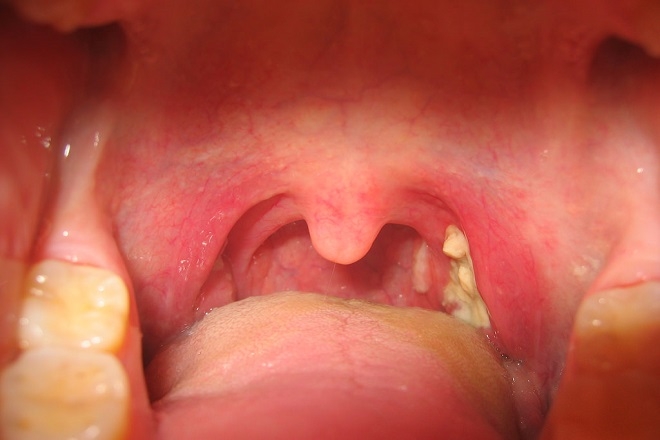

Bệnh bạch hầu là bệnh nhiễm khuẩn, nhiễm độ cấp tính do vi khuẩn bạch hầu gây nên; bệnh thường gặp ở trẻ nhỏ, tuy nhiên cũng có thể gặp ở người lớn nếu không có miễn dịch. Bệnh lây truyền dễ dàng qua đường hô hấp hoặc qua tiếp xúc trực tiếp với các dịch tiết từ niêm mạc mũi họng của bệnh nhân hoặc người lành mang trùng khi ho, hắt hơi, đặc biệt trong khu vực dân cư đông đúc hoặc nơi có điều kiện vệ sinh không đảm bảo. Biểu hiện bệnh có thể từ nhẹ đến nặng, thường có giả mạc màu trắng ở tuyến hạnh nhân, hầu họng, thanh quản, mũi, có thể xuất hiện ở da, các màng niêm mạc khác như kết mạc mắt hoặc bộ phận sinh dục, trường hợp nặng có thể gây biến chứng và tử vong.

![]() |

| Bệnh bạch cầu đơn nhân nhiễm trùng Ảnh minh họa |